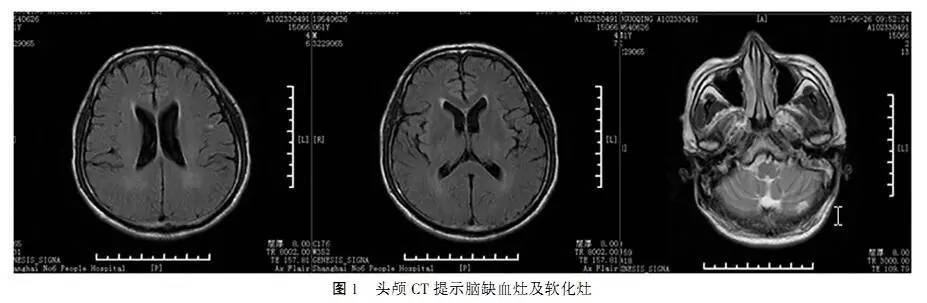

患者3次血尿同步电解质及血尿渗透压结果见表1,发现2次尿钠和尿氯排出增多,2次尿渗透压增高,1次血渗透压降低,另有1次血钠稍偏低(133mmol/L,与减少口服盐胶囊有关)。其余检查包括红细胞压积、肝肾功能、血气分析、甲状腺功能、肾上腺功能、立卧位试验、过夜1mg地塞米松抑制试验、性激素均正常。脑钠肽(BNP)及脑钠肽原(proBNP)也正常。患者入院后复查头颅CT提示:双侧额顶叶、脑室周边白质缺血灶、左小脑软化灶(图1)。垂体MRI提示:部分空泡蝶鞍(图2)。